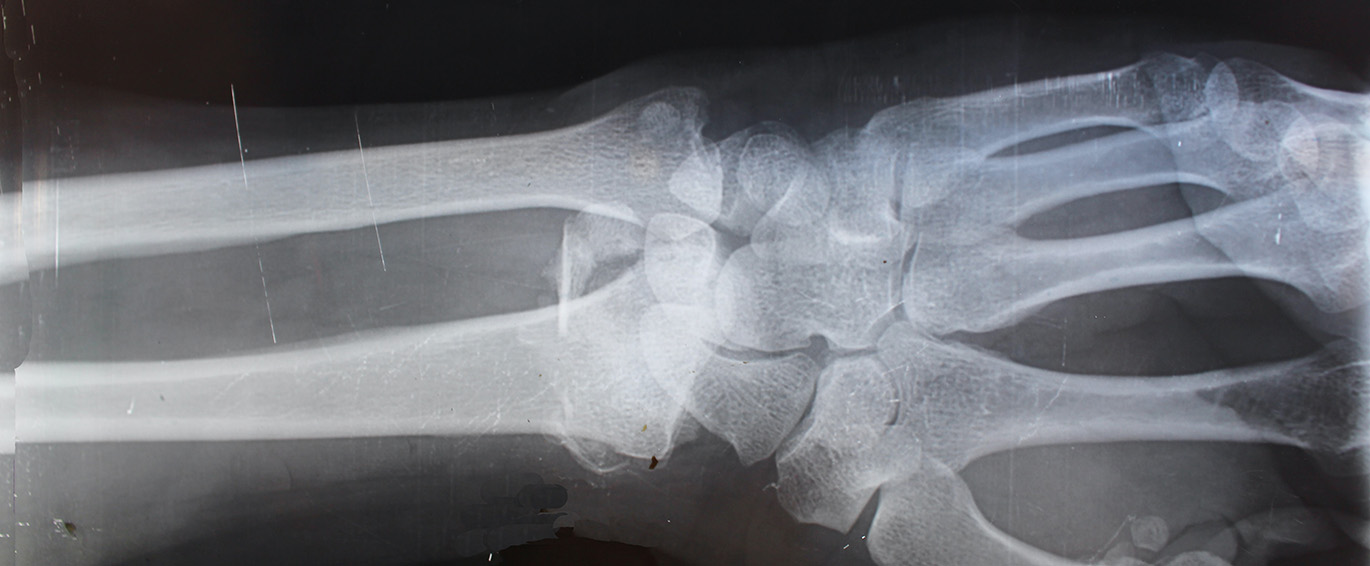

- Os punhos também são facilmente focos de quebras, pois num reflexo, leva-se as mãos a frente do corpo durante a queda. A maior incidência é em mulheres na pós menopausa